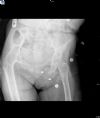

Hip Joint Ankylosis - Axial view - 50 years post TB infection of the joint.

The patient is fully active!

Hip Joint Ankylosis - Axial view - 50 years post TB infection of the joint. The patient is fully active!